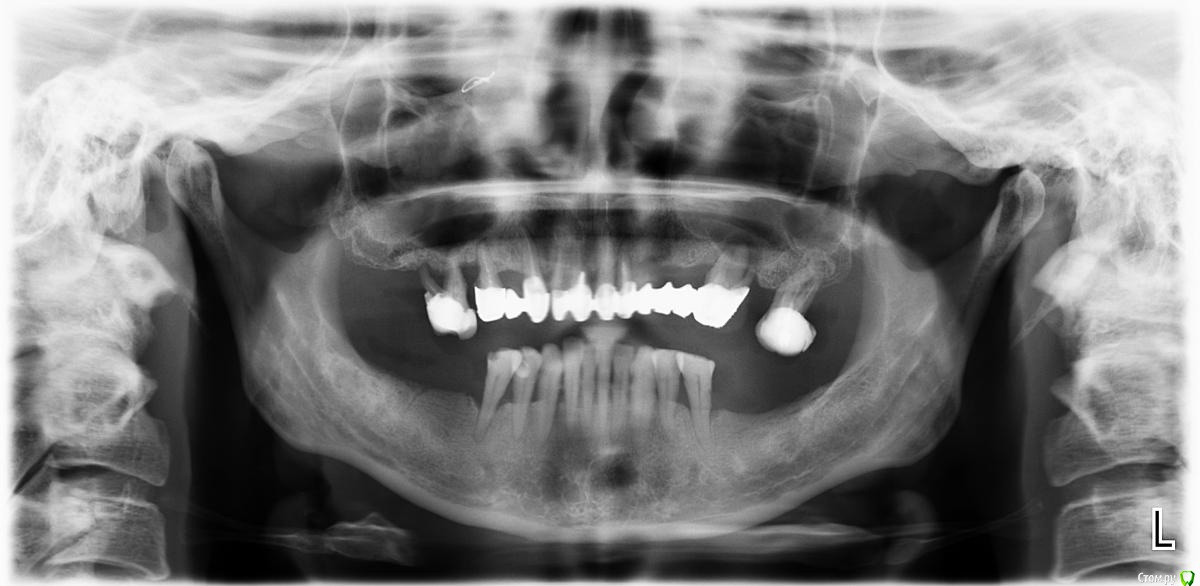

Татьяна_1973 Опубликовано 28 января, 2016 Поделиться Опубликовано 28 января, 2016 Здравствуйте!Интересует вопрос: возможна ли постановка имплантов при таком состоянии зубов и челюсти (все отягощено еще и курением с периодическим бросанием )? Врачи говорят: снимаем мост, удаляем весь верх, постановка имплантов невозможна при таком пародондите (он является абсолютным противопоказанием), только съемная. Лечение не предлагают. Морально совсем не готова "зубы на полку").И был уже опыт отказов от меня в моем городке 12 лет назад, мост делали в соседнем, простоял 12 лет вместо 5-7 обещанных. Тогда тоже здесь говорили, убираем все, делаем съемную. Понимаю, что ситуация не улучшилась, а только ухудшилась. Но, читая форум, предполагаю, что варианты вполне могут быть. На данный момент половина моста просто снимается (как сделал врач при осмотре), потому решать надо сейчас и, если решаться на возможность имплантов, искать врача в радиусе сотен километров .Не знаю, важно или нет, был перелом верхней челюсти права (говоря по-обывательски, альвеолярного отростка - так по-моему правильно?), при первом протезировании (12 лет назад) отказ в постановке имплантов был именно по этой причине: что они однозначно не приживутся (перелом случился за год до начала протезирования). Заранее большое спасибо Ссылка на комментарий

Evikrol Опубликовано 28 января, 2016 Поделиться Опубликовано 28 января, 2016 Для планирования имплантации необходима трёхмерная компьютерная томограмма. Но думаю что на верхней челюсти можно поставить "все на 4" с одномоментным удалением и мплантацией. Временный несъёмный протез будет готов в течении недели. 2 Ссылка на комментарий